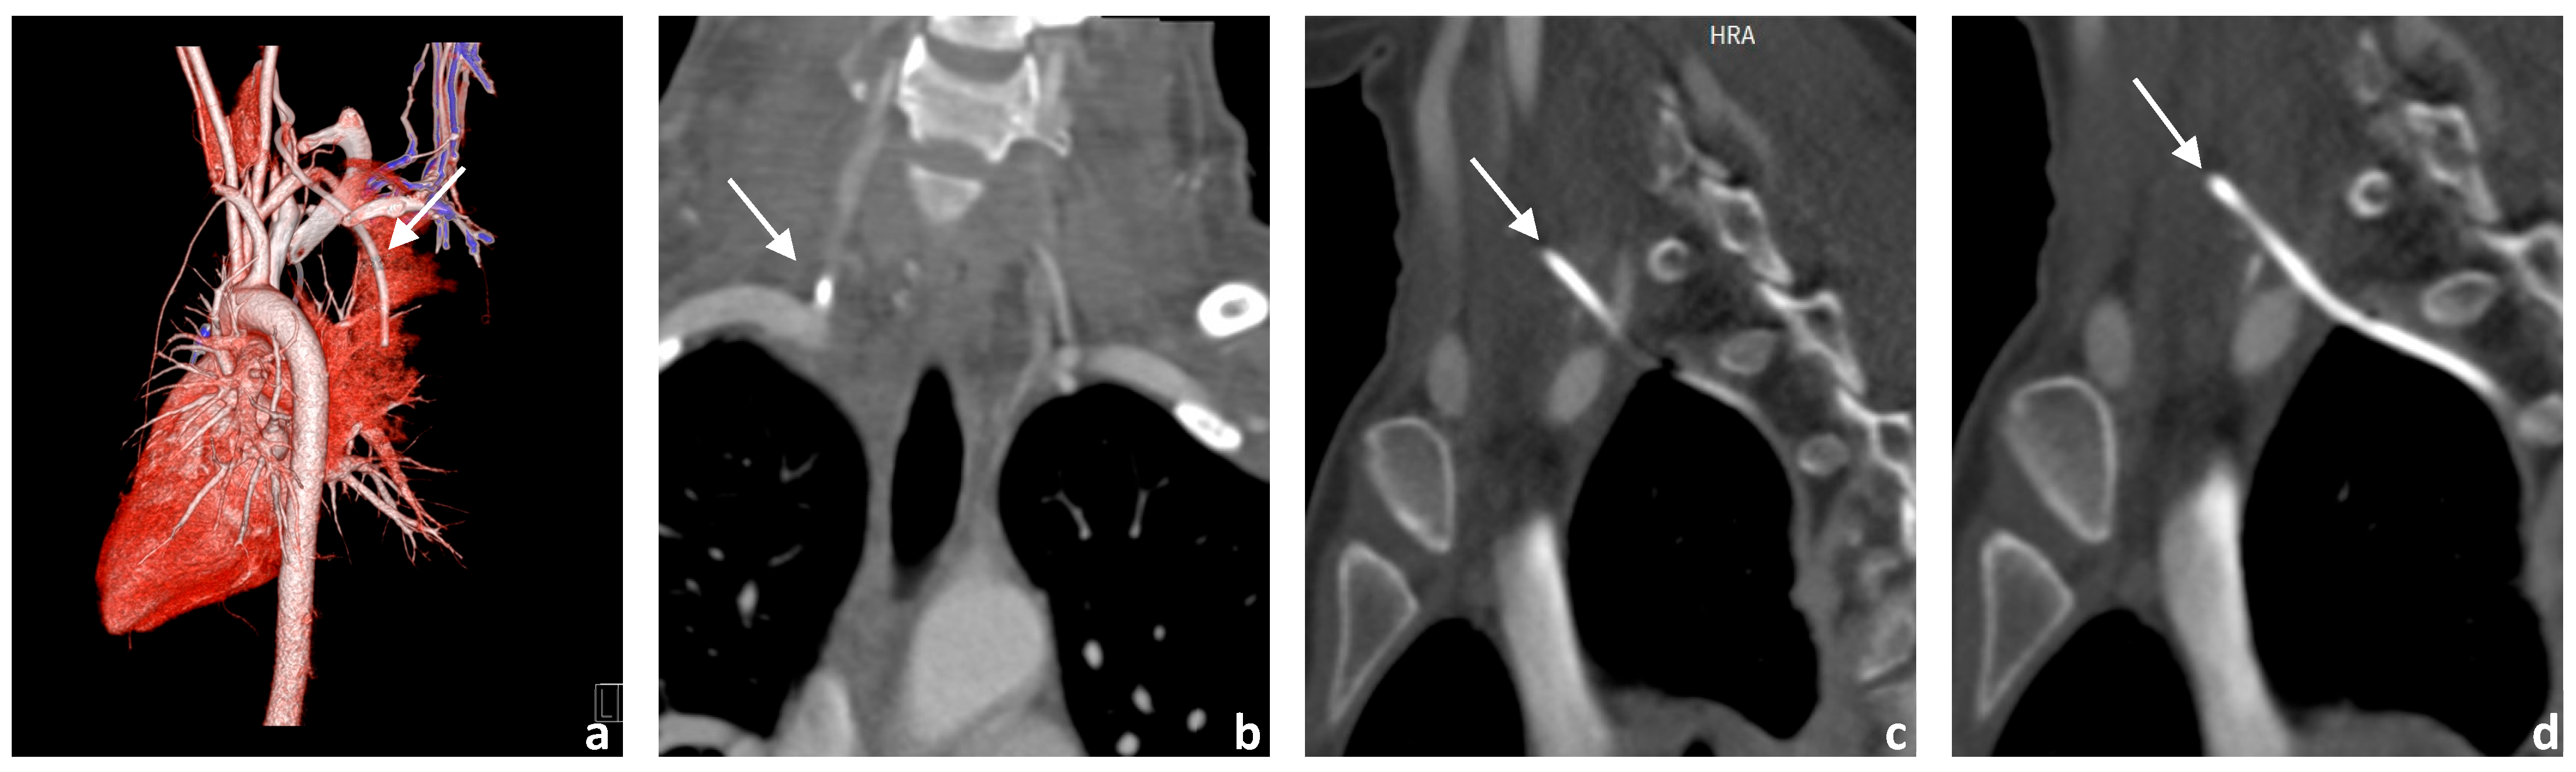

3.1. Image Acquisition